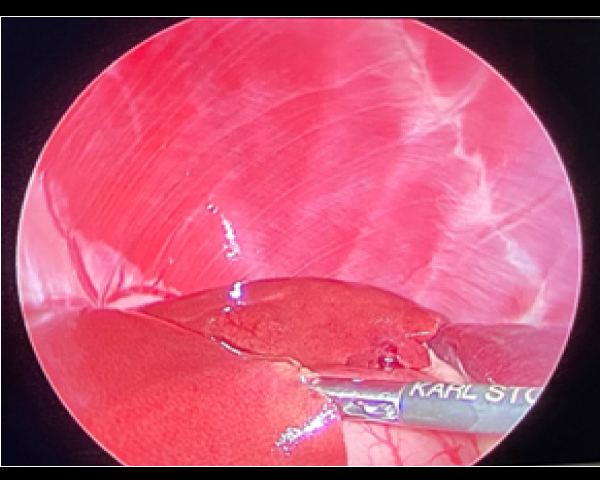

胸腔鏡で覗くと胸管がキレイに見えます(黒矢印)。

これを鉗子で丁寧に剥離していきます

反対側も同じように剥離していきます。

必ず、反対側の胸管も確認できるところまで剥離します。(黒矢印)

反対側もクリップ3-4本止めて、結紮します。

これで胸管結紮は終了です